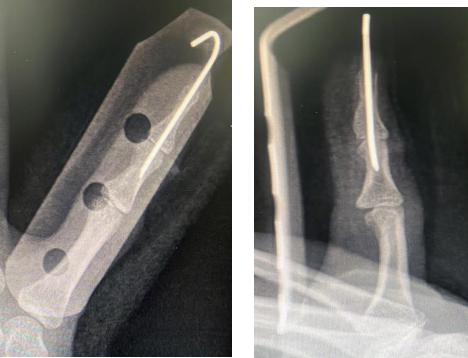

Fig: 2a,Fig: 2b

X-ray of the fifth finger right hand AP and lateral views

Fig: 4a, Fig: 4b

Fig: 5a , Fig: 5b

Postoperative x-rays

Post-operative x-ray confirmed good position of DIP joint with K wire insitu (figure 5a and 5B)